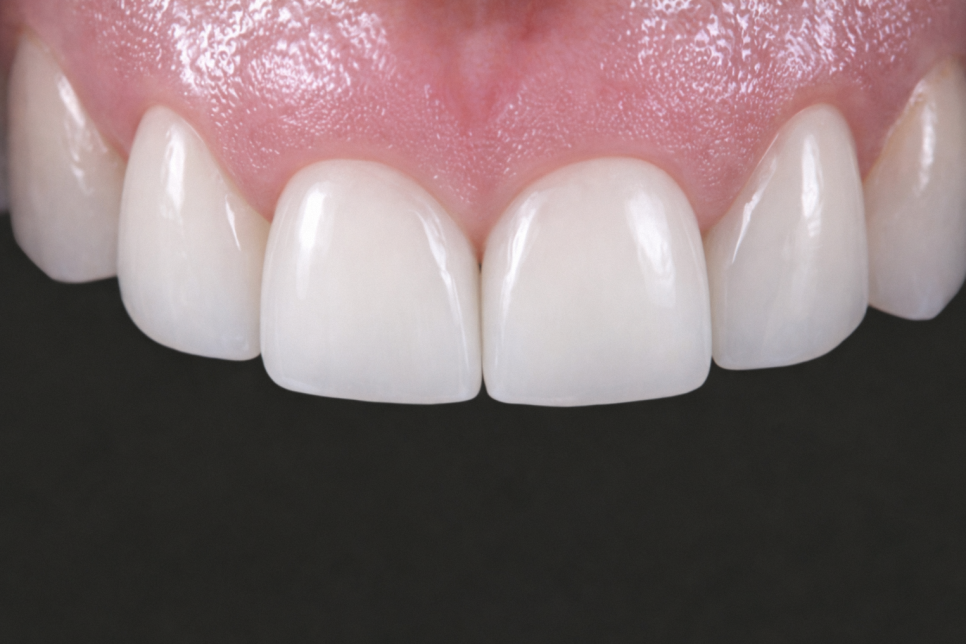

- 라미네이트가 필요한 경우

손상 범위가 더 넓거나

심미성의 중요도가 높은 분에게는

라미네이트를 권유 드립니다.

자연치 겉면을 얇게 다듬은 뒤

얇은 세라믹 재료를 덧붙이는 방법입니다.

앞니는 작은 차이만 있어도 부각되기 때문에,

라미네이트의 얇고 정밀한 마감이

심미적인 완성도를 높이는 데 유리합니다.

강도와 변색 가능성도 적기 때문에

장기적으로 외형을 유지할 수 있습니다.